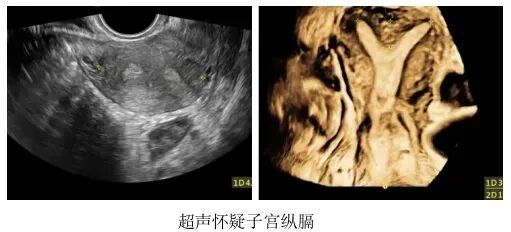

(3)子宫畸形

纵膈子宫与鞍型子宫均属于常见的子宫形态异常,其中纵膈子宫又分为完全纵膈和不完全纵膈两种类型。

• 完全纵膈:就是在子宫中间有一道“墙”,把“一间房”强行分成“两间房”,而这个更小的宫腔环境往往因为太小,而不能满足胚胎着床和发育的需求。

• 不完全纵膈:则是指这堵墙封的并不完整,还有一半或者一部分,仍保持连通状态。

• 鞍型子宫:是指这堵墙只有地基,并未形成明显的宫腔分隔。

虽然不完全纵膈子宫和鞍型子宫的影响通常小于完全纵膈子宫,但在部分情况下仍可能对生育造成干扰。

一般来说,纵膈越大,就越需要进行宫腔镜手术来修正子宫形态,帮助怀孕。